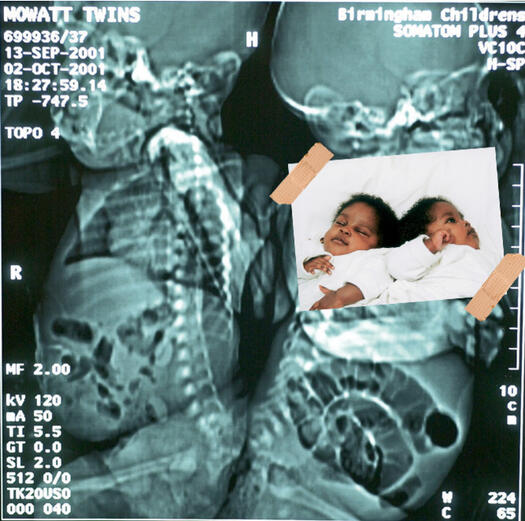

ЕКСПОНАТ 5

Човек в човека

Сестрите Моват от Великобритания се раждат през 2002 година. Свързани са с долната част на гръбнака, лекарите веднага режат и днес момичетата са напълно самостоятелни девойки в пубертета, които тровят родителите си.